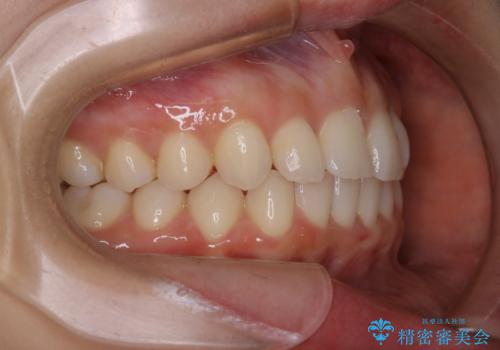

動きづらい前歯のねじれもマウスピース(インビザライン)で改善

- 前から2番目の歯が捻じれていることが気になるとご相談にいらした方です。

インビザラインFULLで治療を行いました。

上の前から2番目の歯は、一般的に周囲の歯と比べて小さく、動きづらい歯であると言われています。前歯にゴムかけを行うことで理想的な位置まで歯を動かしてくることが出来ました。